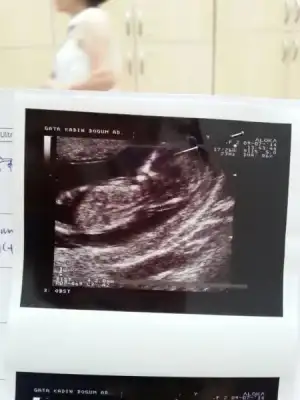

Resimleri ekte. Doktor bi tahminde bulundu, bakalım sizlerin yorumu ne olacak. Normalde 11+5 ama 12+1 olarak gözüküyor.

Kizlar oniki haftalikken cekildi bunlar su anda 16 oldum hala soylemedi doktor.gorememis bakalim siz gorebilcek misiniz?